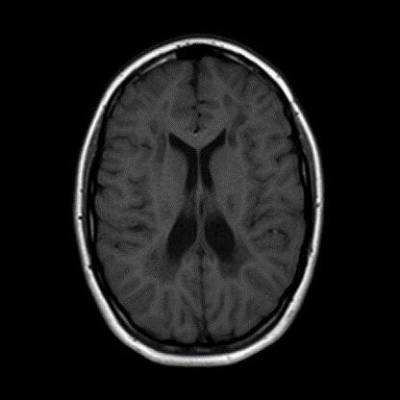

- A) Aksiyel T2A ve koronal T2A sekanslarda sentrum semiovale, korona radiata ve bazal ganglionlar düzeyinde bilateral frontoparietal derin periventriküler beyaz cevherde birleşme eğilimi gösteren hiperintens gliotik sinyal değişiklikleri (oklar) ve aksiyel T2A serilerde servikal spinal kordda posterior kolonda, lateral kesimlerde sinyal artımları (oklar) izlendi.

- B) Kontrastsız T1A serilerde tarifli alanlarda hipointens (oklar) görünüm izlendi. Kontrastlı T1A serilerde bu düzeyde (oklar) kontrastlanma artışı izlenmedi. Diffüzyon ağırlıklı serilerde belirgin diffüzyon kısıtlaması (oklar) görülmedi.

- Etkilenen bölgelerde T1’de hipointens, T2/FLAIR’da hiperintens sinyal değişiklikleri izlenir. DWI’de lezyonların periferinde kısıtlı difüzyon görülebilir. MRS’de beyaz cevherde laktat artışı saptanabilir, ancak bu her hastada mevcut değildir.